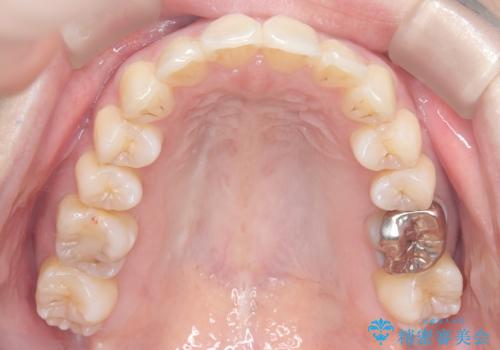

- 患者様は、上顎前歯の突出を改善したいとのご希望で来院されました。診断の結果、噛み合わせや全体的な歯列には大きな問題がないため、上顎のみを対象とした部分矯正が最適と判断しました。特に患者様は短期間での治療完了を希望されていたため、治療期間を約半年と設定しました。審美ワイヤーを用い、前歯を後方に移動させることで、自然で整った仕上がりを目指しました。治療計画は、患者様のスケジュールや希望を最大限考慮し、実現可能な目標を設定しました。

部分矯正では、治療範囲が限定されるため、力のコントロールが非常に重要です。本症例では、前歯を後方に移動させる際、周囲の歯や噛み合わせに影響を及ぼさないように細心の注意を払いました。また、短期間の治療でも歯の移動に伴う歯肉や歯根への負担を抑えるため、定期的なチェックと調整を行いました。患者様には矯正装置の清掃を徹底していただき、虫歯や歯周病のリスクを回避しました。結果として、予定通りの期間で治療を完了し、患者様には満足していただけました。